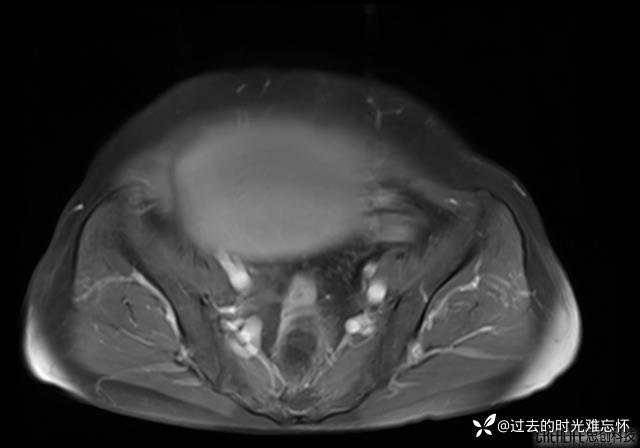

患者性别:女

患者年龄:65岁

主诉: 发现腹部隆起半年余。无其他明显不适。

浆液性囊腺瘤 (22)